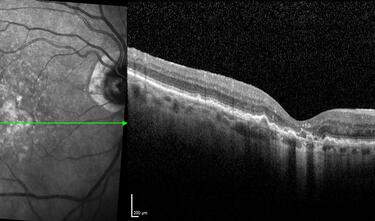

Clase 15 - Depósitos y signos específicos en DMAE no neovascular

Clase 16 - Distrofia hereditarias de la retina que simulan DMAE no neovascular

Clase 18 - Signos estructurales diferenciales entre neurodegeneración y exudación en DMAE

Clase 20 - Signos clave en patología traccional vítrorretiniana

Clase 21 - Desprendimiento de vítreo y desprendimiento de retina